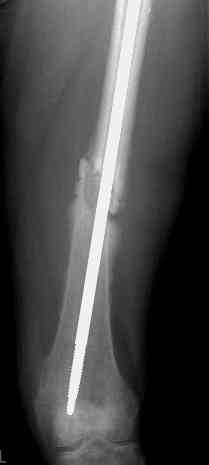

История больного, о котором я говорил выше. Не удивляйтесь изложенному

Больной А., 28 лет, поступил в НИИ им. Н.В. Склифосовского 22.12.99 после падения на улице. Жалобы на боли в области левого тазобедренного сустава и левом бедре. Из анамнеза следовало, что 20.06 во время прыжка с парашютом у него возник закрытый оскольчатый перелом средней трети левой бедренной кости со смещением отломков, по поводу чего в одной из ЦРБ Московской области через 3 дня после травмы был произведен открытый интрамедуллярный остеосинтез штифтом типа Кюнчера.

Послеоперационное течение было гладким. Больной ходил при помощи костылей с дозированной нагрузкой на оперированную конечность.При осмотре в НИИ им. Н.В. Склифосовского через 6 месяцев после травмы:

левое бедро и левый коленный сустав несколько увеличены в объеме, отечны, пальпаторно определяется болезненность в средней трети бедра;

по его наружной поверхности послеоперационный рубец - рана зажила первичным натяжением. При измерении длины бедер обнаружено укорочение левого бедра на 4,5 см. На рентгенограммах этого бедра: ось конечности правильная, отмечается захождение основных костных фрагментов по длине, проксимальный конец штифта выступает слишком медиально и высоко относительно большого вертела, периостальная мозоль незначительна.22.12 - через 6 месяцев после операции, произведенной в ЦРБ, нами по поводу замедленно консолидирующего перелома левой бедренной кости с ее абсолютным укорочением под наркозом произведена операция: удаление штифта, закрытый блокирующий интрамедуллярный остеосинтез перелома левого бедра штифтом без рассверливания (UFN) длиной 40 см, диаметром 10 мм с блокированием только проксимальных отверстий (динамический остеосинтез). Наложен аппарат Илизарова на 4 полукольцах с целью удлинения укороченного бедра. Послеоперационное течение без особенностей. Ежедневно осуществляли дистракцию отломков на 1 мм. Через 3 недели после операции больной выпи-сан на амбулаторное лечение с продолжением дистракции отломков. В течение 1,5

месяцев дистракции укорочение левого бедра удалось полностью устранить. 22.02.00, т.е. через 2 месяца после повторного остеосинтеза, больному произведено дистальное блокирование штифта двумя винтами и демонтирован аппарат Илизарова. В течение 2 недель после операции больной ходил с помощью костылей, потом 2 недели с тростью. Опороспособность и функция оперированной конечности полностью восстановились через 4 недели после операции.

Фиксаторы удалены через 12 месяцев после операции, выполненной по поводу замедленной консолидации перелома бедра с его укорочением.